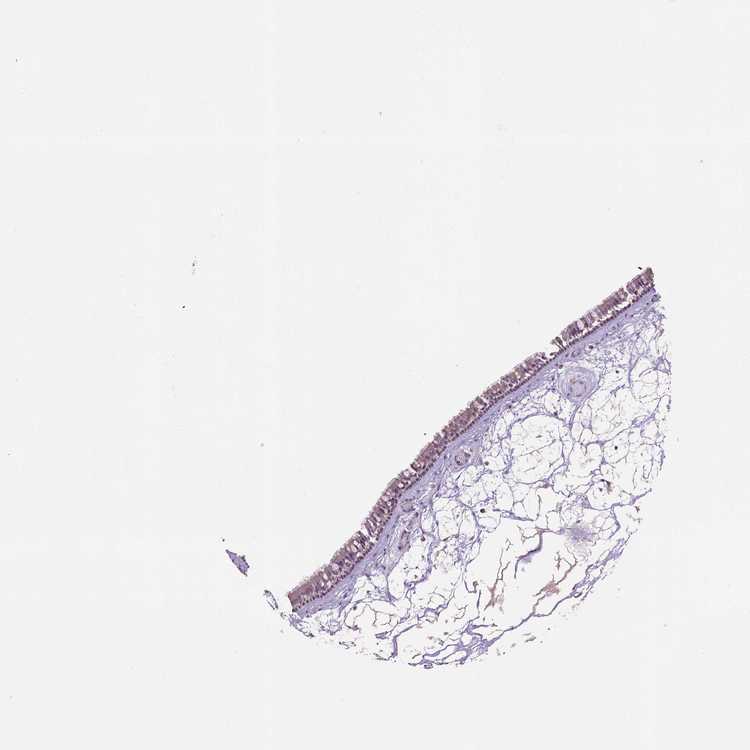

TISSUE PRIMARY DATA NASOPHARYNX Show tissue menu

NASOPHARYNX - Antibody stainingi

Antibody staining in the annotated cell types in the current human tissue is reported as not detected, low, medium, or high, based on conventional immunohistochemistry profiling in selected tissues. This score is based on the combination of the staining intensity and fraction of stained cells.

Each image is clickable and will lead to virtual microscopy that enables deeper exploration of all samples and also displays staining intensity scores, fraction scores and subcellular localization as well as patient and tissue information for each sample.

Antibody HPA039158

Respiratory epithelial cells Not detected